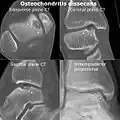

-

CT scan and projectional radiography of a case of osteochondritis dissecans of parts of the superior-medial talus. -

Computed tomography (CT) scans and Technetium-99m bone scans are also sometimes used to monitor the progress of treatment. Unlike plain radiographs (X-rays), CT scans and MRI scans can show the exact location and extent of the lesion.[39] Technetium bone scans can detect regional blood flow and the amount of osseous uptake. Both of these seem to be closely correlated to the potential for healing in the fragment.[40][41]